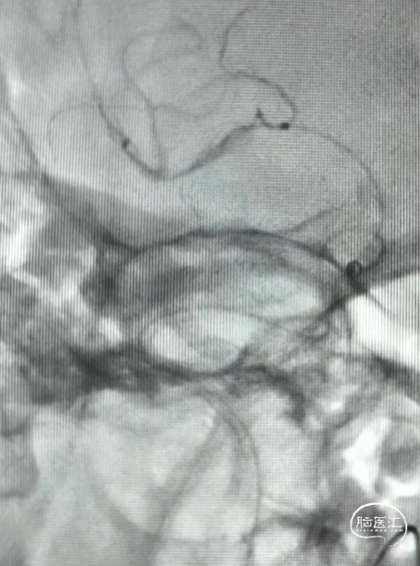

DSA造影(2024.11.07)

右侧颈内动脉起始段闭塞,动脉晚期可见颈动脉颅内段浅淡显影。

前交通动脉开放,右侧大脑中动脉显影良好。

右侧后交通动脉开放,右侧颈动脉颅内段浅淡显影。

释放4.0*30mm Syphonet®取栓支架

2.5*15mm SacSpeed®球囊扩张导管在C5段进行球囊扩张

2.5*15mm SacSpeed®球囊扩张导管在C1段进行球囊扩张

清理管腔血栓

回收4.0*30mm Syphonet®取栓支架